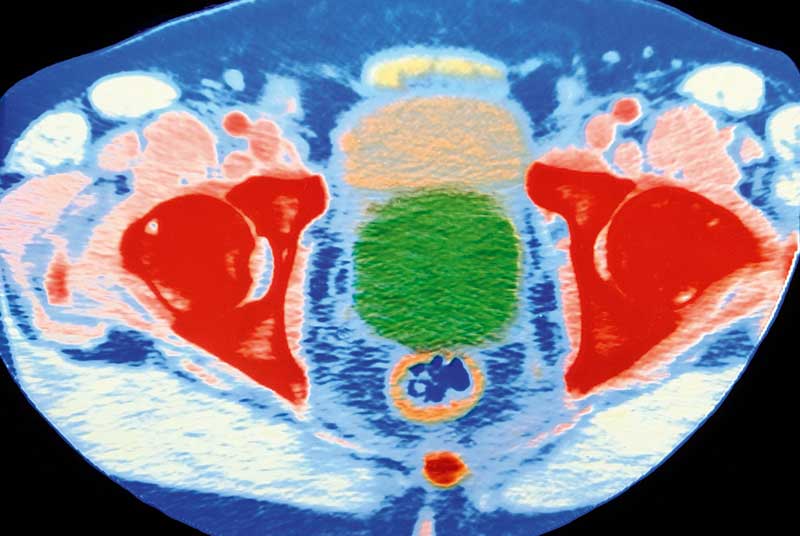

Col Ct Scan Of Enlarged Prostate Gland With Cancer Photograph by Dept Ct Scan Prostate Prostate cancer screening is typically a psa blood test. Once a prostate cancer diagnosis has been made, your doctor works to determine the extent (stage) of the cancer. On imaging, the upper limit of normal is considered to be 30 ml 16. This test isn’t often needed for. The prostate comprises 70% glandular tissue and 30%. Learn how biopsy, ultrasound,. Ct Scan Prostate.